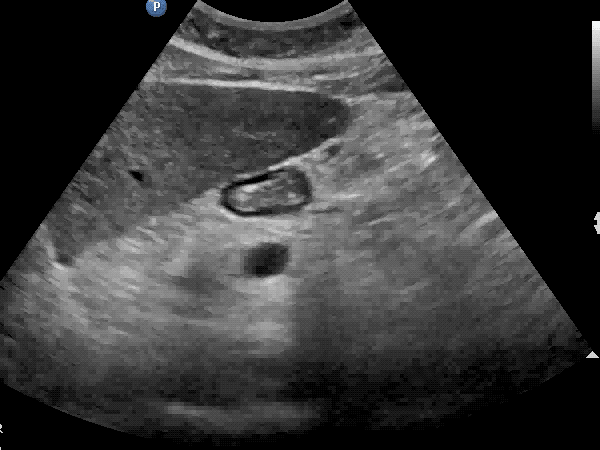

- Is the stomach empty or full ?

- If clear fluid is present in the stomach – calculating the volumen in the stomach

- Does the content in the stomach represent a risk for the patient ?